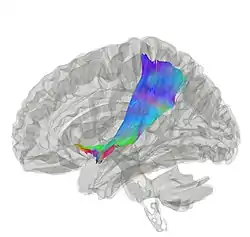

Tractography showing extreme capsule fibers | |

The extreme capsule (Latin: capsula extrema) is a series of nerve tracts between the claustrum and the insular cortex.[1] It is also described as a thin capsule of white matter as association fibres.[2] The extreme capsule is separated from the external capsule by the claustrum, and the extreme capsule separates the claustrum from the insular cortex, and all these lie lateral to the corpus striatum components.[2][3]

From the midline of the brain to the side, the extreme capsule is the outermost from the external capsule and the inner internal capsule.[4]

It is most easily visible in a horizontal section, just lateral to the claustrum.